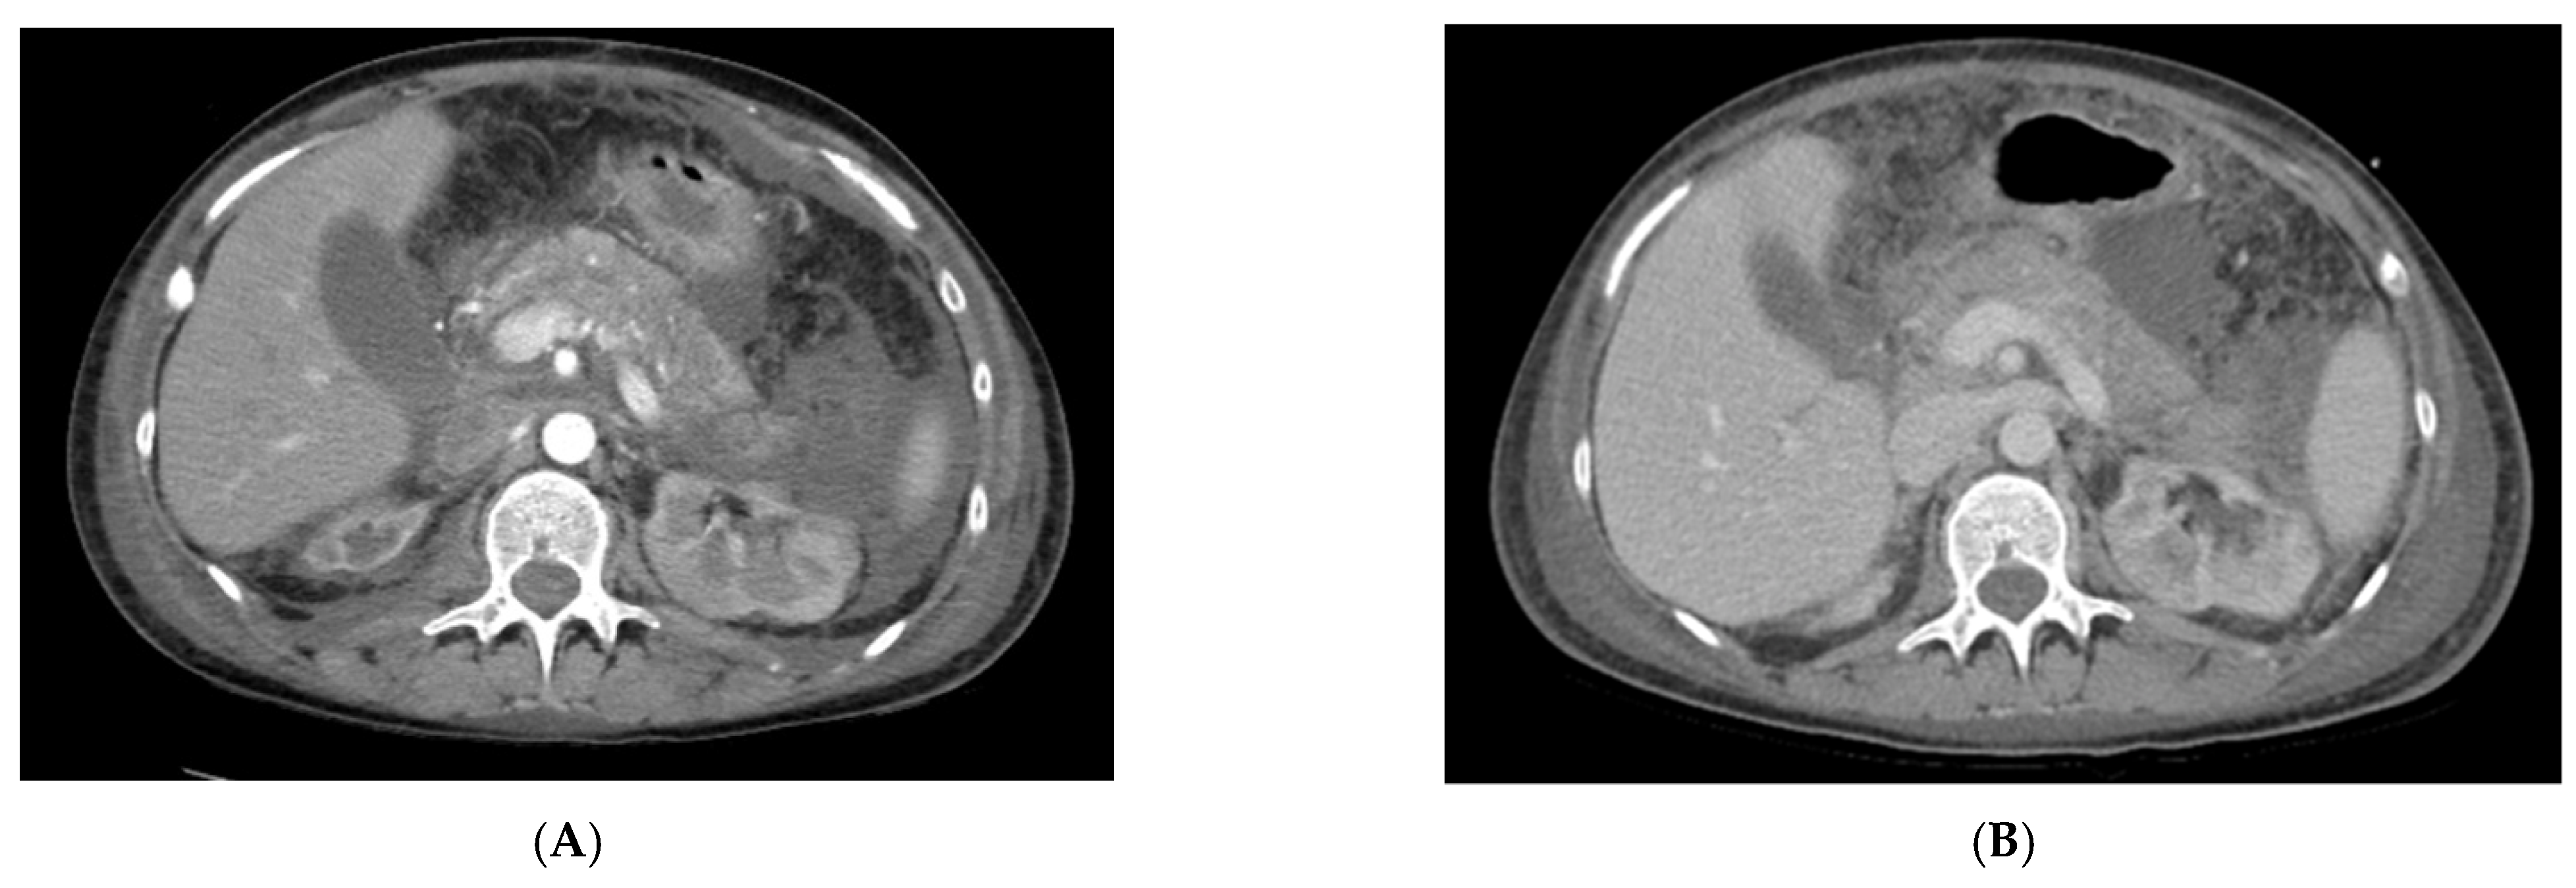

On admission, lab tests revealed mild anemia, lymphopenia, and inflammatory syndrome defined by increased levels of C-reactive protein (CRP), D-dimers, and lactate dehydrogenase (LDH). Renal and liver function tests were in the normal range. Extended biological parameters on admission and the trends are listed in Table 1. A thoracic native computer tomography (CT) scan revealed moderate pneumonia affecting 30% of the lungs (Figure 2A). The thoracic CT scan showed bilateral pleural effusions (Figure 2B). Based on these findings, together with the positive RT-PCR and respiratory failure, the diagnosis of a severe form of COVID-19 pneumonia was established. Following delivery, further investigations revealed elevated lipase levels of 2273 IU/L, which were three times higher than the normal value. Clinical and biological data were in favor of acute pancreatitis as indicated by the Atlanta definition [6]. The diagnosis was confirmed by a contrast-enhanced abdominal CT scan, which revealed a pancreas with increased volume and edema, with exudative changes causing liquid collections anterior and posterior to the pancreatic head and within the peritoneal cavity without signs of infection or abscesses (Figure 3A). The diagnosis of AP was established with the following severity scores: SAPS = 17 (2.6%), APACHE = 7 (7.6%), and SOFA = 1 (<10%).

An abdominal US performed on day 16 and day 18 concluded that the patient developed necrotizing pancreatitis complicated by a pancreatic abscess. A CT scan confirmed the presence of the abscess (Figure 3B).

On day 25, slow unfavorable progression indicated the need for a repeat abdominal CT scan, which showed progressive, necrotizing pancreatitis accompanied by intra-abdominal and parietal wall abscesses. The lab test results indicated marked inflammatory syndrome, severe anemia, prolonged coagulation screening, and deteriorating renal function.

Figure 3. Abdominal CT scan in evolution. (A) Initial contrast-enhanced CT scan showing diffuse pancreatic edema and peripancreatic liquid collection. (B) Native CT scan revealing inhomogeneous pancreas characteristic of necrotizing pancreatitis, peripancreatic and retroperitoneal collection, and moderate ascites.